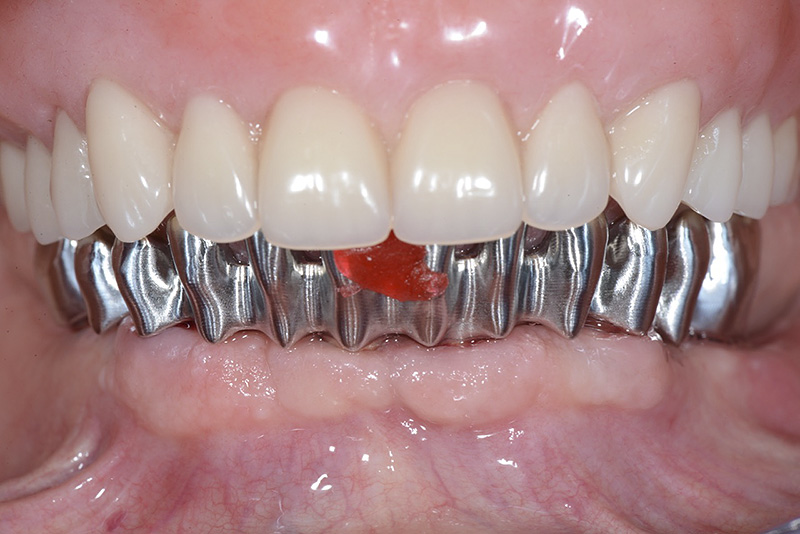

PREMESSA: in seguito all’estrazione dell’incisivo laterale superiore di destra, resasi necessaria per cause batteriche, si decide di affrontare il caso con il posizionamento di un impianto in sostituzione dell’elemento mancante dopo guarigione del sito infetto. Con tecniche rigenerative sia dei tessuti ossei mancanti a causa dell’infezione pregressa, sia dei tessuti gengivali che appaiono inizialmente troppo spostati in alto, si ripristina una corretta morfologia delle parabole (contorni) gengivali e delle papille interdentali (triangoli di gengiva tra due denti vicini).

Vengono utilizzati 2 tipi di provvisori: il primo, cementato ai denti vicini, viene utilizzato dal momento dell’estrazione del dente fino ad impianto osteointegrato (circa 6 mesi); il secondo, avvitato direttamente all’impianto, ha una funzione di prova estetica ma soprattutto di guida per la maturazione dei tessuti gengivali peri-implantari portandoli verso la maturazione completa prima di posizionare la corona finale in disilicato di litio.